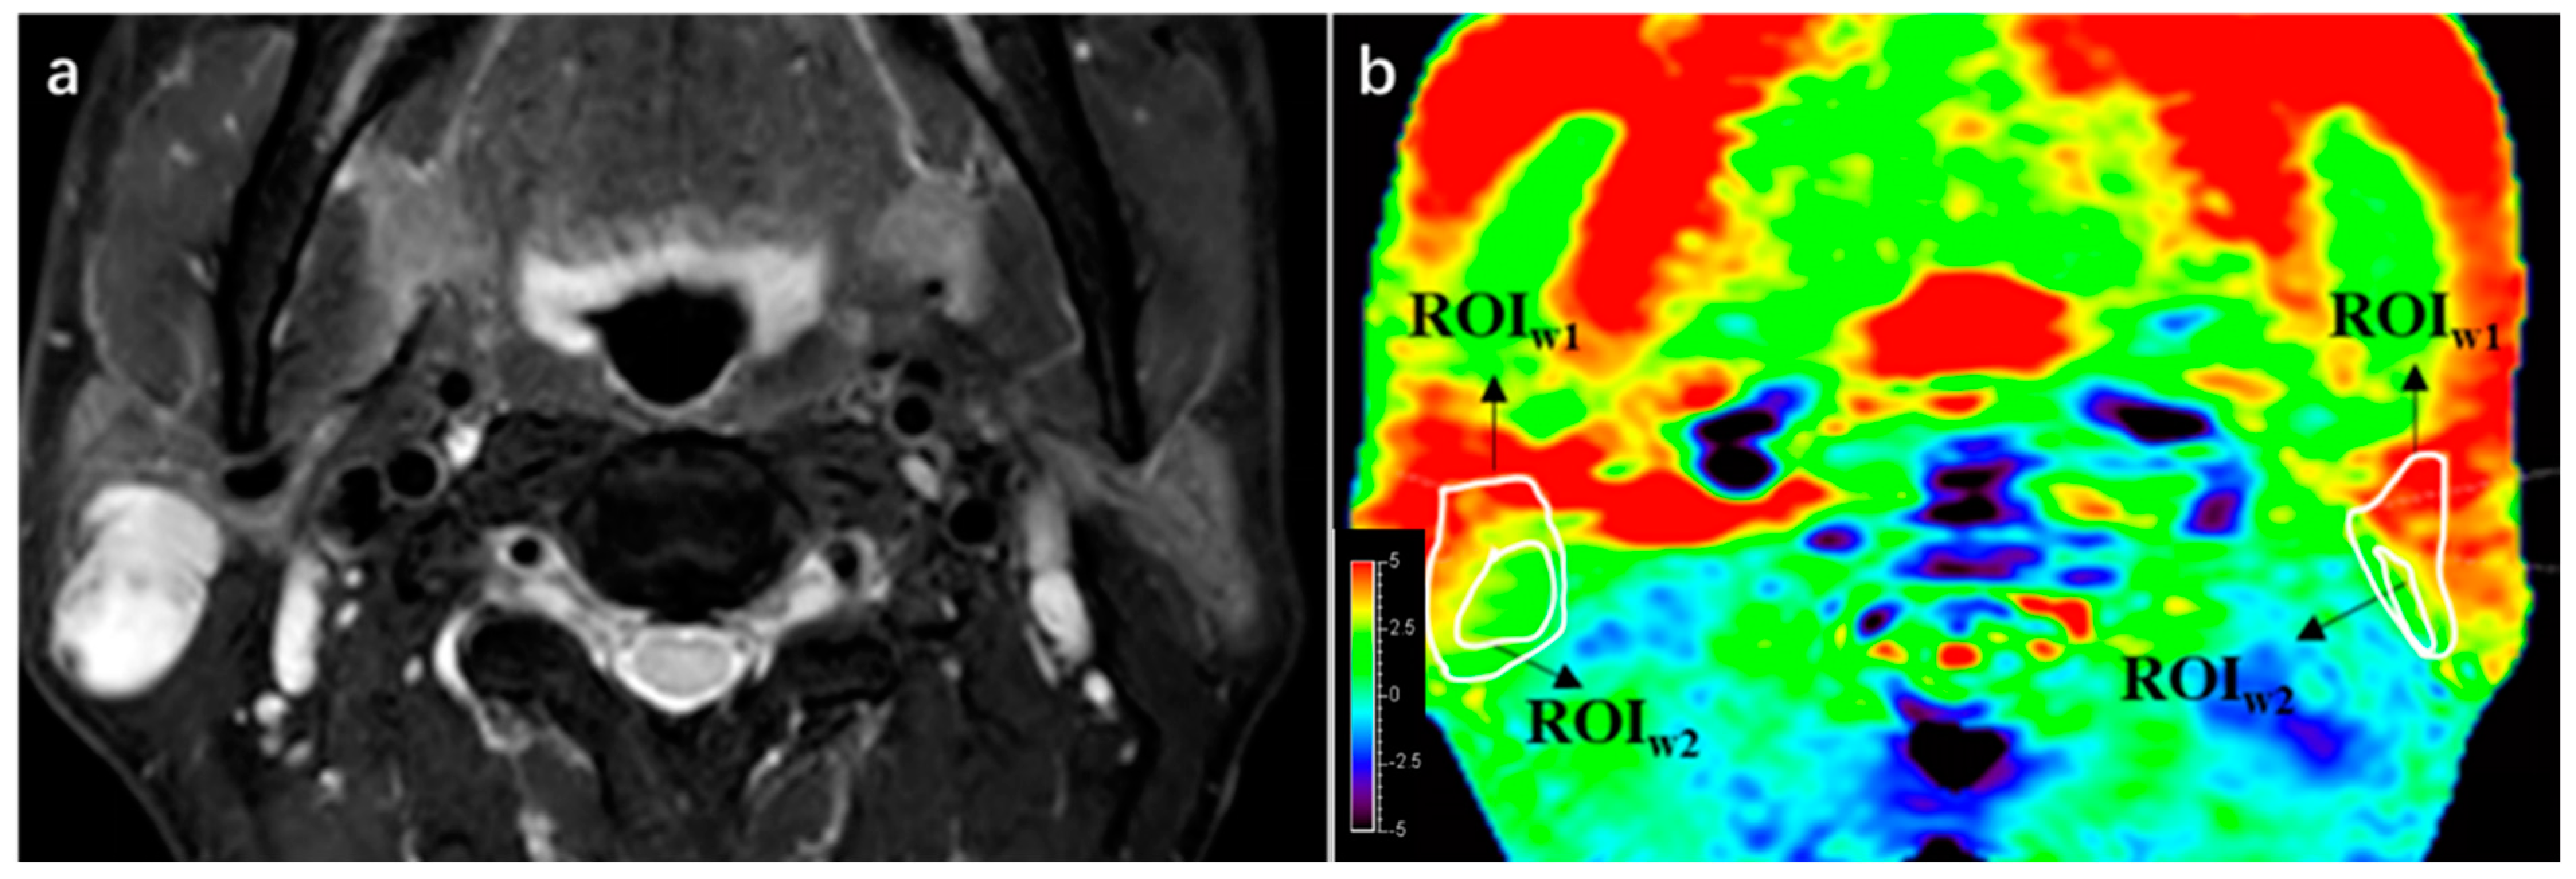

For qualitative analysis, the region of interest (ROI1) of each PG and PT was manually delineated based on the T2W images by the two radiologists. ROI2 was drawn in such a way as to maintain the most parotid gland or lesion area while excluding most of the hyperintensity artifacts (Figure 2).

Figure 2.

An example of ROI1 and ROI2 drawn in a patient with WT and image quality score. (a) A lesion was found at right side of parotid gland in this 55-year-old male on T2WI. (b) ROI1 of both the lesion and parotid gland were delineated in APTw sequence 1 imaging according to T2WI, then ROI2 was drawn inside ROI1, maintaining the greatest area of normal gland or lesion while deleting hyperintensity areas. Integrity scores of both lesion and parotid were 4, considering that the entire lesion and parotid gland were displayed. Hyperintensity of lesion and parotid gland were both 3.